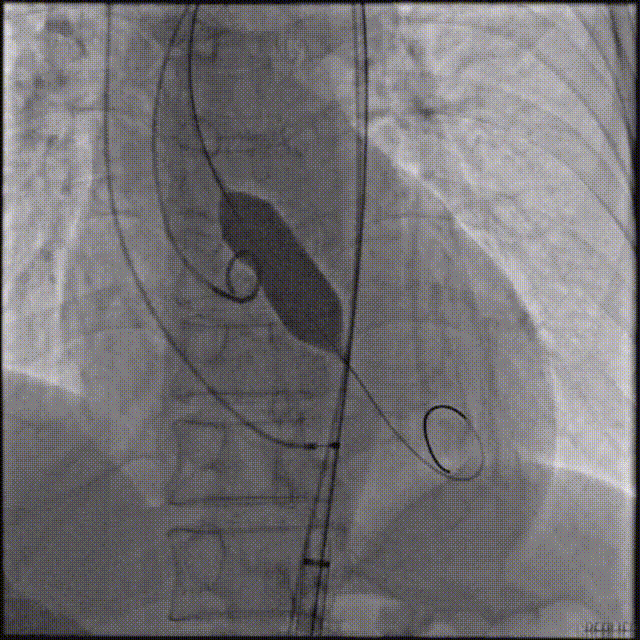

主动脉根部造影,采用20mm球囊预扩,有明显腰征,无造影剂渗漏。

主动脉根部造影

球囊预扩

TaurusElite输送系统轻松过弓、跨瓣,AV23瓣膜瓣环上约2-4mm释放。

瓣膜初始位置释放

回收再定位释放

第一次释放到工作位后瓣膜下滑,回收调整位置后选择高位再次释放,最终造影显示瓣膜形态、位置良好,冠脉血流灌注正常,超声提示少量瓣周漏。